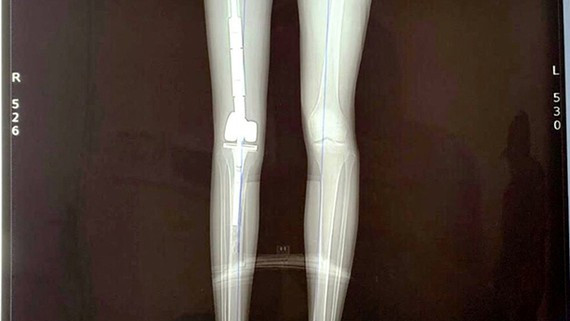

Ngày 10/10, Bệnh viện Trung ương Quân đội 108 thông tin các bác sĩ tại đây vừa thực hiện thành công kĩ thuật ghép thận tự thân - một bước tiến đột phá của y học và là ca đầu tiên được ghi nhận tại Việt Nam.